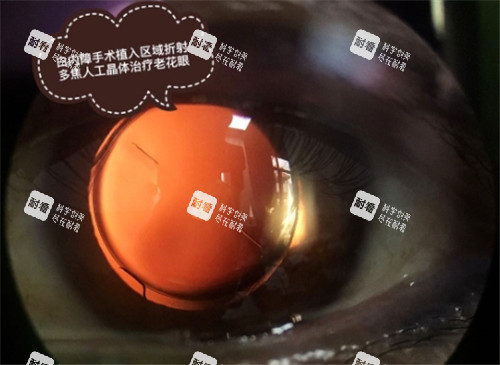

(2)白内障诊疗

作为医院的重点特色项目,开展普通超声乳化白内障手术、飞秒辅助白内障手术,同时提供多种价位的人工晶体选择,满足不同患者的需求。

飞秒辅助白内障手术+进口折叠晶体:8800元/单眼起

高端多焦点人工晶体置换:12800元/单眼起